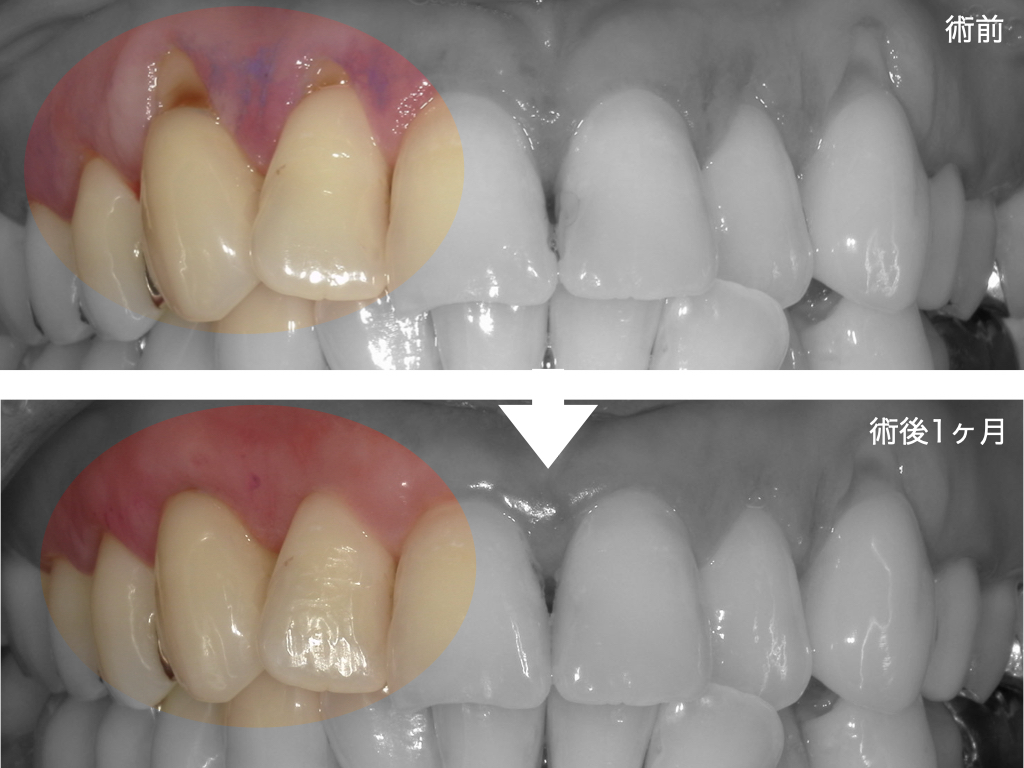

・年齢・性別:30代・女性

・主訴:前歯の歯ぐきが下がって見た目が気になる。冷たいものがしみる。

患者様は、「歯茎が下がっているのが気になって、思いっきり笑えない。」という審美的な悩みと、冷水痛(知覚過敏)を訴えて来院されました。

治療結果

・歯肉の位置が回復し、歯の長さのバランスが改善

・知覚過敏の軽減

・歯肉の厚みが増加し、再発リスク低下

見た目だけでなく「機能的にも改善」している点が重要と考えています。